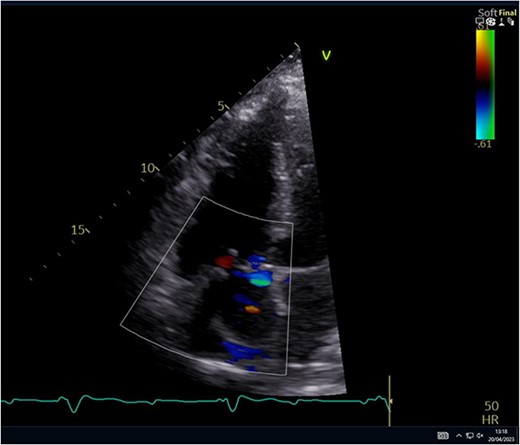

A 29-year-old man with a history of ventricular septal defect closure as a child, presented with severe multi-organ injuries after being run down by two cars. He was intubated on the scene by the hospital emergency medical services before being taken to the emergency department for haemodynamic stabilization and multiple imaging procedures. He suffered extensive bilateral degloving scalp lacerations and a haematoma due to bleeding from his left temporal artery. Computed tomography scan revealed bilateral multilevel rib fractures, a left-sided flail segment, bilateral haemopneumothoraces, and multifocal lung contusions, for which bilateral intercostal chest drains were inserted. Moreover, he had a shallow pneumopericardium, a subcapsular left renal haematoma, an extraperitoneal pelvic hematoma, displaced right-sided superior and inferior pubic ramus fractures as well as slight diastasis of the left sacroiliac joint. Although maximum resuscitation measures were taken with adequate fluid and blood product resuscitation, he remained persistently hypotensive and had worsening haemodynamics despite maximal inotropic support. A transoesophageal echocardiogram demonstrated a flail anterior leaflet of the TV and ruptured papillary muscle head (Fig. 1) with torrential tricuspid regurgitation (TR) and high right atrial (RA) pressures (Fig. 2).

The leaflet was excised and a 27 mm Mitral Magna Ease tissue valve was implanted. He was successfully weaned off cardiopulmonary bypass and decannulated off ECMO in sinus rhythm. Post-operative ECHO showed a well seated and functioning TV prosthesis (Fig. 4).